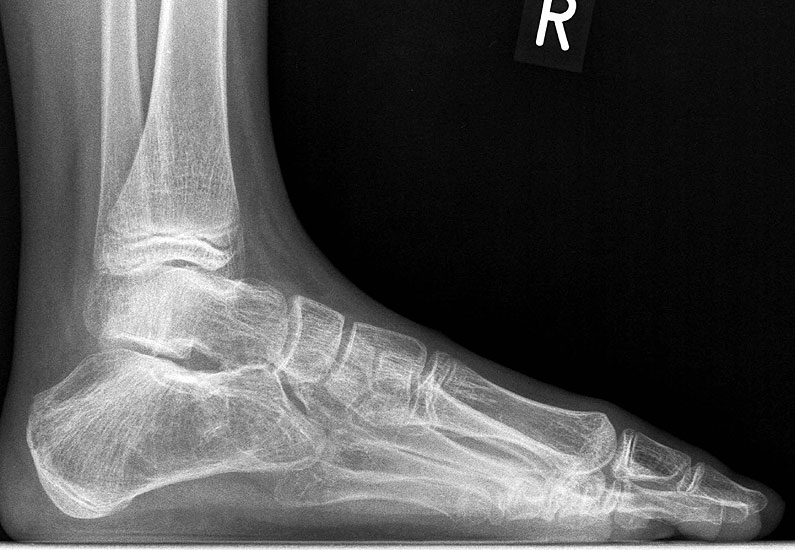

Die bildgebende Primärdiagnostik ist die Röntgen-Übersichtsaufnahme des Fußes im seitlichen, dorsoplantaren und schrägen Strahlengang. Weitere in der Literatur beschriebene Röntgen-Spezialeinstellungen sind durch die modernen dreidimensionalen Verfahren überholt.

Diagnostisch sollte neben Röntgenübersichtsaufnahmen (indirekte radiologische Zeichen: Dorsaler Traktions-Osteophyt am Taluskopf, „talar beaking“; kontinuierliche Linie der Trochlea-tali-Kontur übergehend in die Sustentaculum-tali-Kontur, „C-Zeichen“ (Abb. 11) 10) immer die dreidimensionale Bildgebung eingesetzt werden. Das MRT (mit Kontrastmittel) kann die Struktur der Brückenbildung und z.B. die Qualität des Restgelenkes (Knorpel-Dicke) besonders gut abbilden; das Dünnschicht-CT zeigt die knöcherne Feinstruktur im Bereich der Coalitio und den oft sehr schrägen Spalt-Verlauf im Frontalschnitt dagegen häufig genauer. Meist findet sich die Überbrückung im Bereich der medialen Facette; die Schichten sollten jedoch bis weit nach dorsal beurteilt werden, da ansonsten dorsomediale Formen übersehen werden können. Rozansky et al 7 unterschieden fünf morphologische Typen auf der Basis von 3-D-CT-Rekonstruktionen. Allerdings ist eine prognostische Zuordnung bisher nicht möglich.